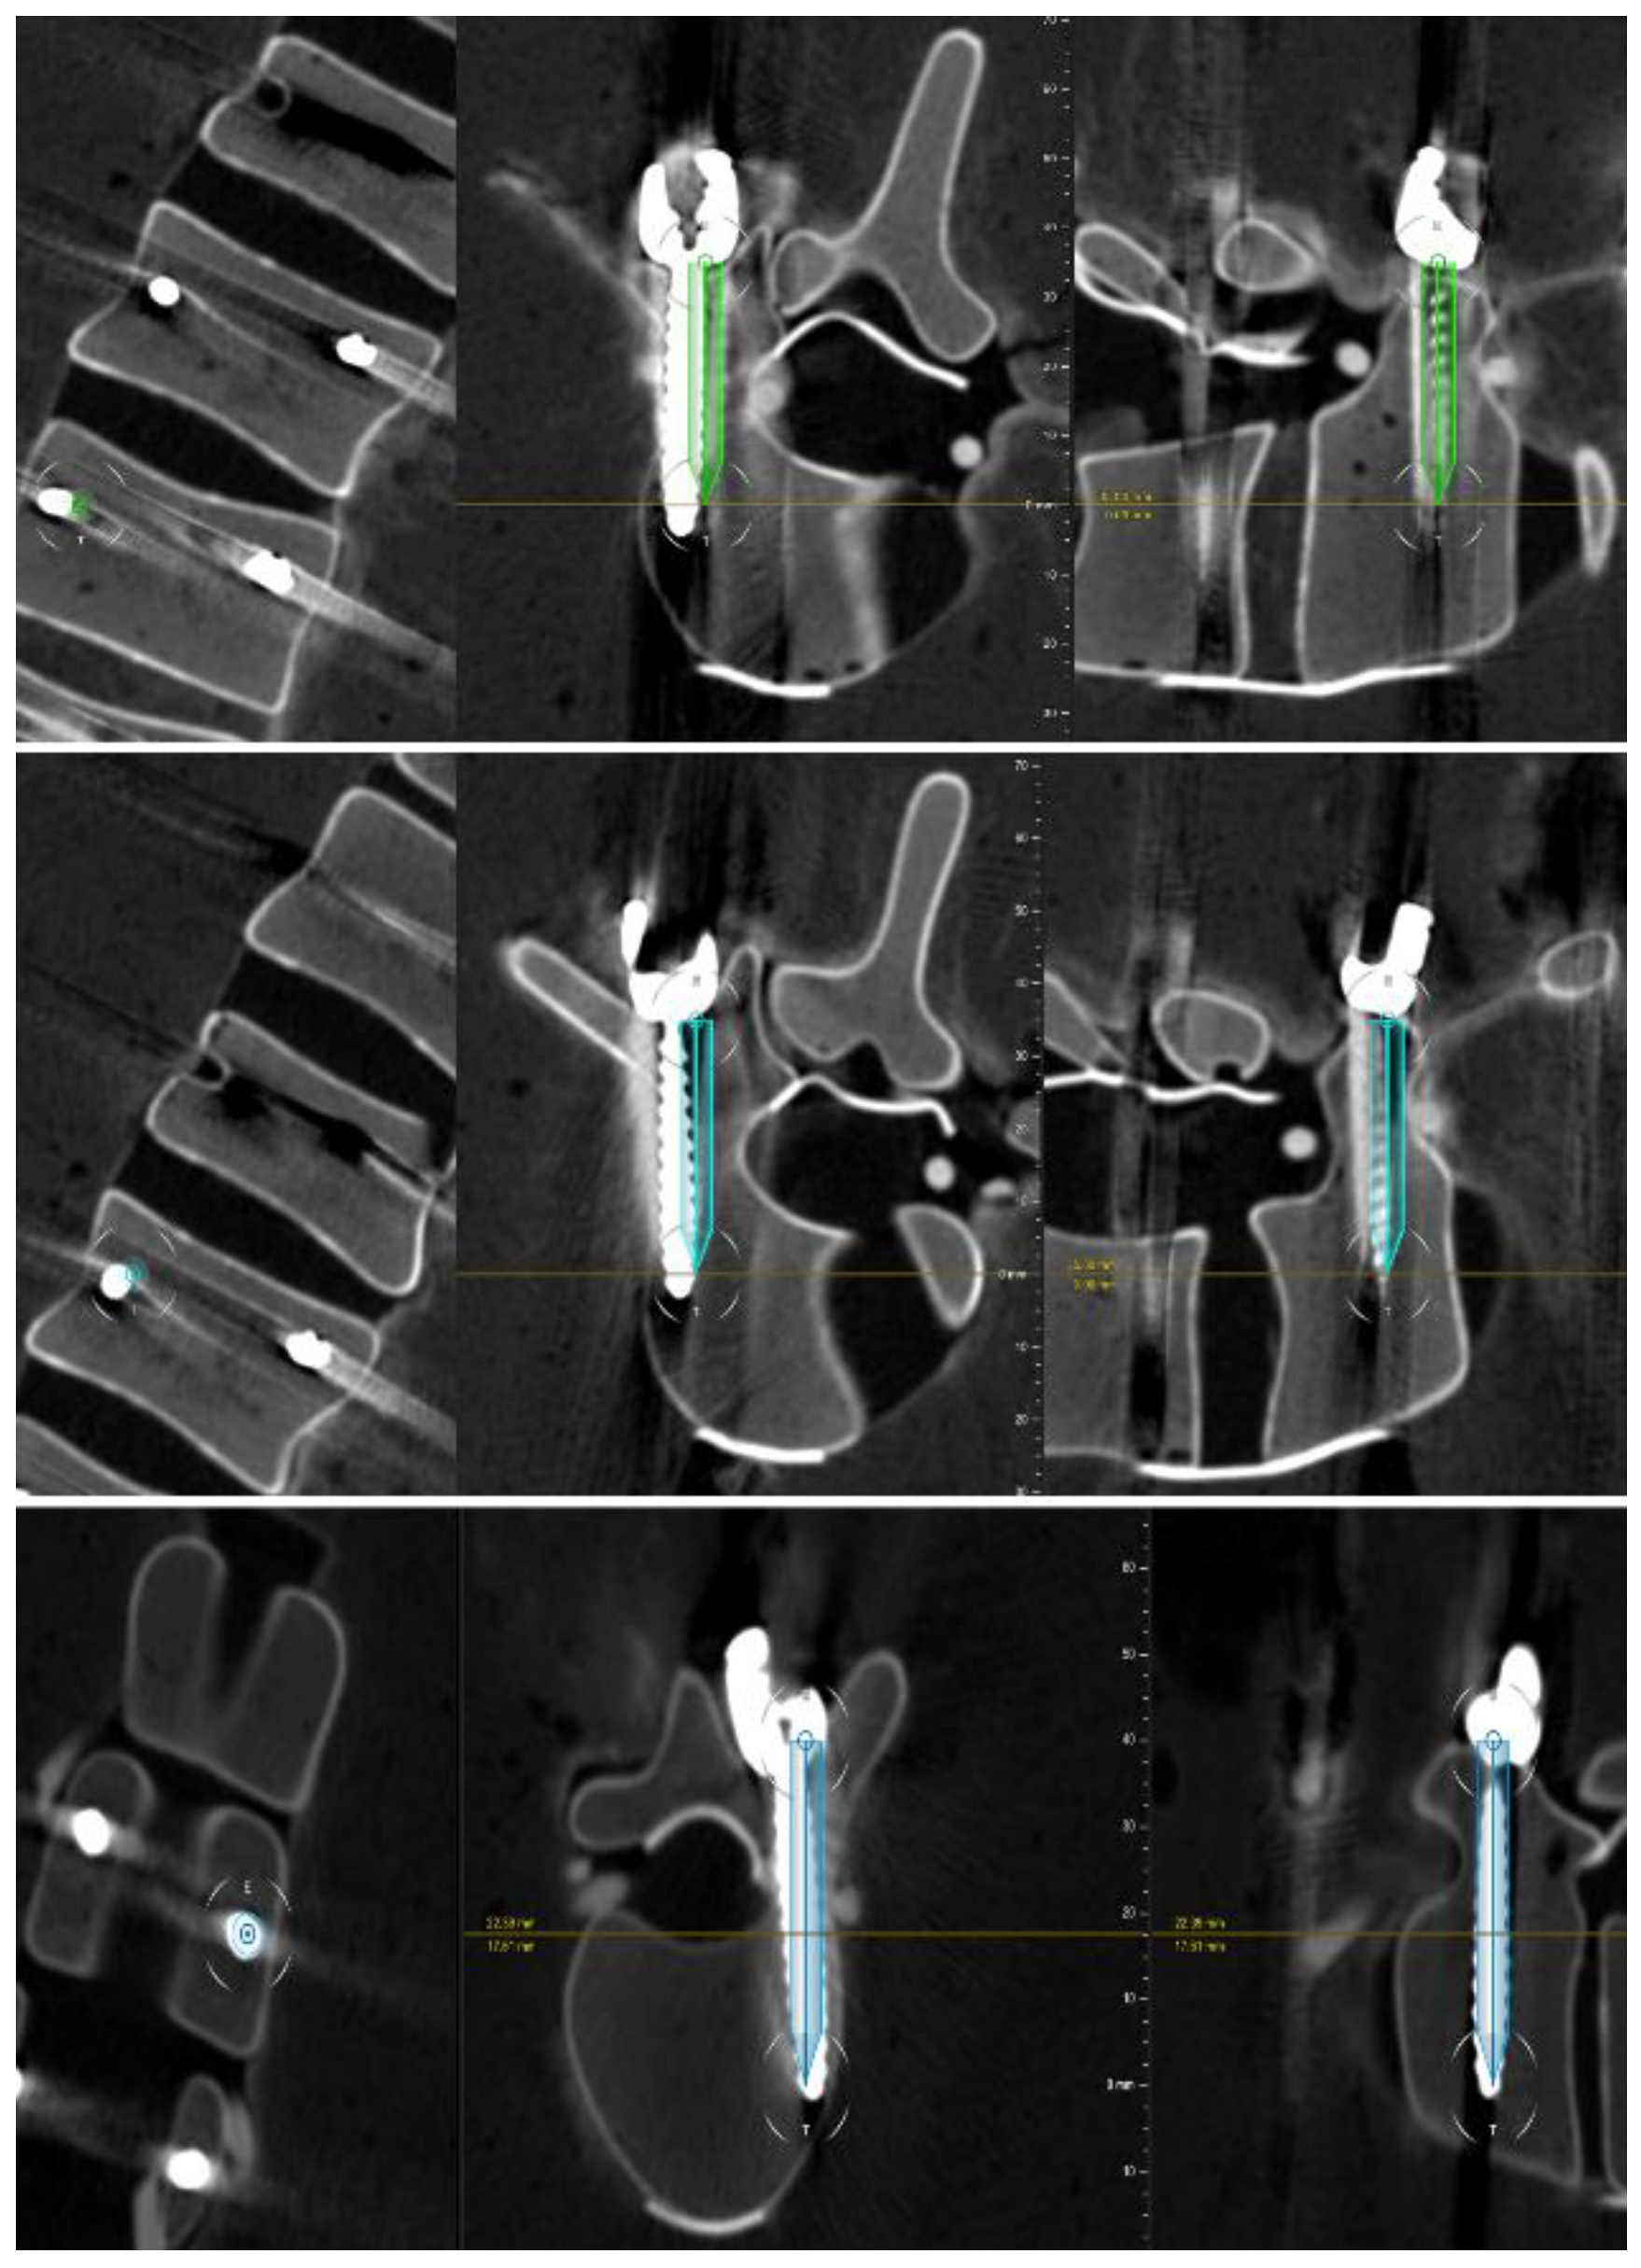

2.2.4. Technical and Clinical Accuracy Evaluation

3.1. Technical Accuracy

3.3. Clinical Accuracy